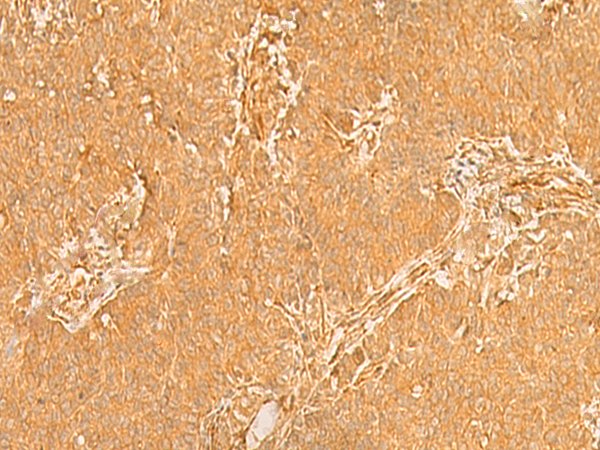

ELISA, IHC |

IHC positive control: |

Human breast cancer and Human ovarian cancer |

IHC Recommend dilution: |

50-300 |